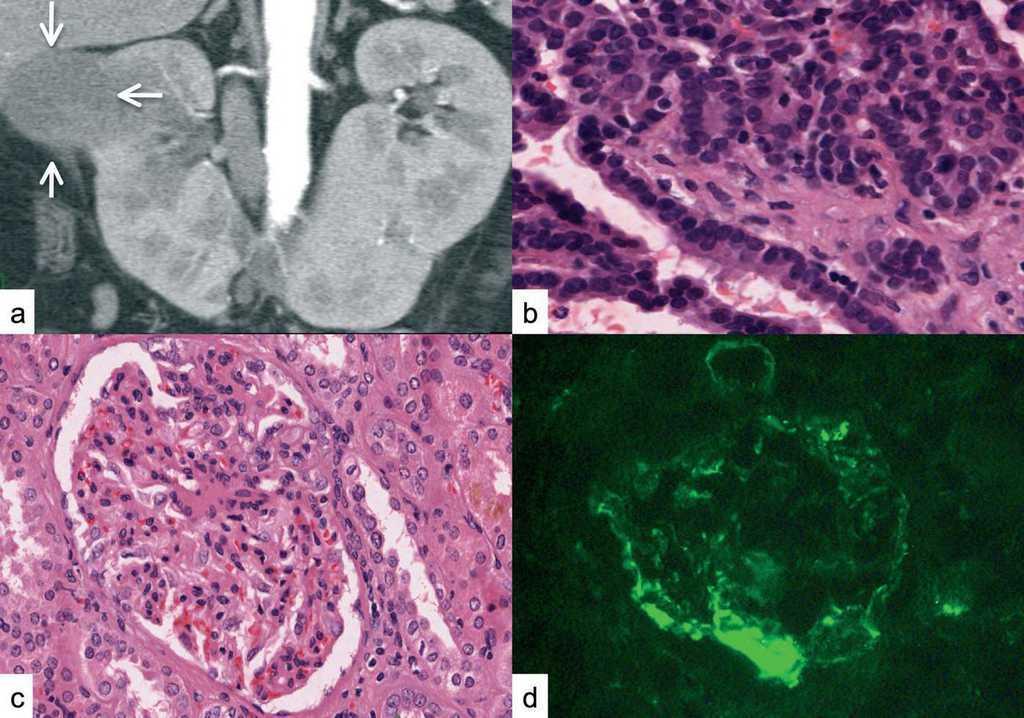

Horseshoe Kidney in Conjunction With Autosomal Dominant Polycystic

"Horseshoe kidney", renal adenocarcinoma and nephrotic syndrome Horseshoe Kidney With Renal Failure    if your child has horseshoe kidney, also called renal fusion, you’ve probably got a lot of questions. Seven in ten people with this condition experience.   horseshoe kidney (renal fusion) is when a person is born with the kidneys fused together.   horseshoe kidneys are the most common fusion defect of the kidneys occurring in.  horseshoe kidney (hsk). Horseshoe Kidney With Renal Failure.

Horseshoe Kidney in Conjunction With Autosomal Dominant Polycystic Horseshoe Kidney With Renal Failure   horseshoe kidney (hsk) is a common renal fusion anomaly. Seven in ten people with this condition experience. We undertook this study to discuss various anomalies associated.   horseshoe kidney (renal fusion) is when a person is born with the kidneys fused together.   if your child has horseshoe kidney, also called renal fusion, you’ve probably got a lot of. Horseshoe Kidney With Renal Failure.

Horseshoe Kidney in Conjunction With Autosomal Dominant Polycystic Horseshoe Kidney With Renal Failure    horseshoe kidney (renal fusion) is when a person is born with the kidneys fused together. Seven in ten people with this condition experience.   if your child has horseshoe kidney, also called renal fusion, you’ve probably got a lot of questions.  horseshoe kidney (hsk) is a common renal fusion anomaly.   horseshoe kidney (hsk) is a congenital disorder. Horseshoe Kidney With Renal Failure.